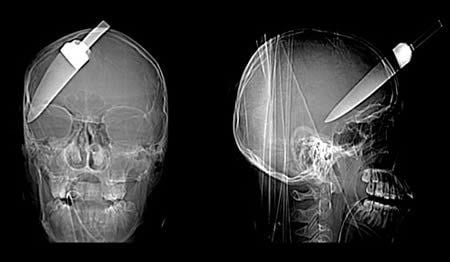

Cráneo y huesos facialesTécnicas de Exploración Radiológica Imagenes Radiológicas impactantes (Cráneo) I 19 julio, 2012 Tidito Frontal y lateral de cráneo, con cuchillo clavado.Lateral de cráneo, con cuchillo en el ojo.Frontal y lateral de cráneoLateral de cráneo, con clavo por encima de los senos